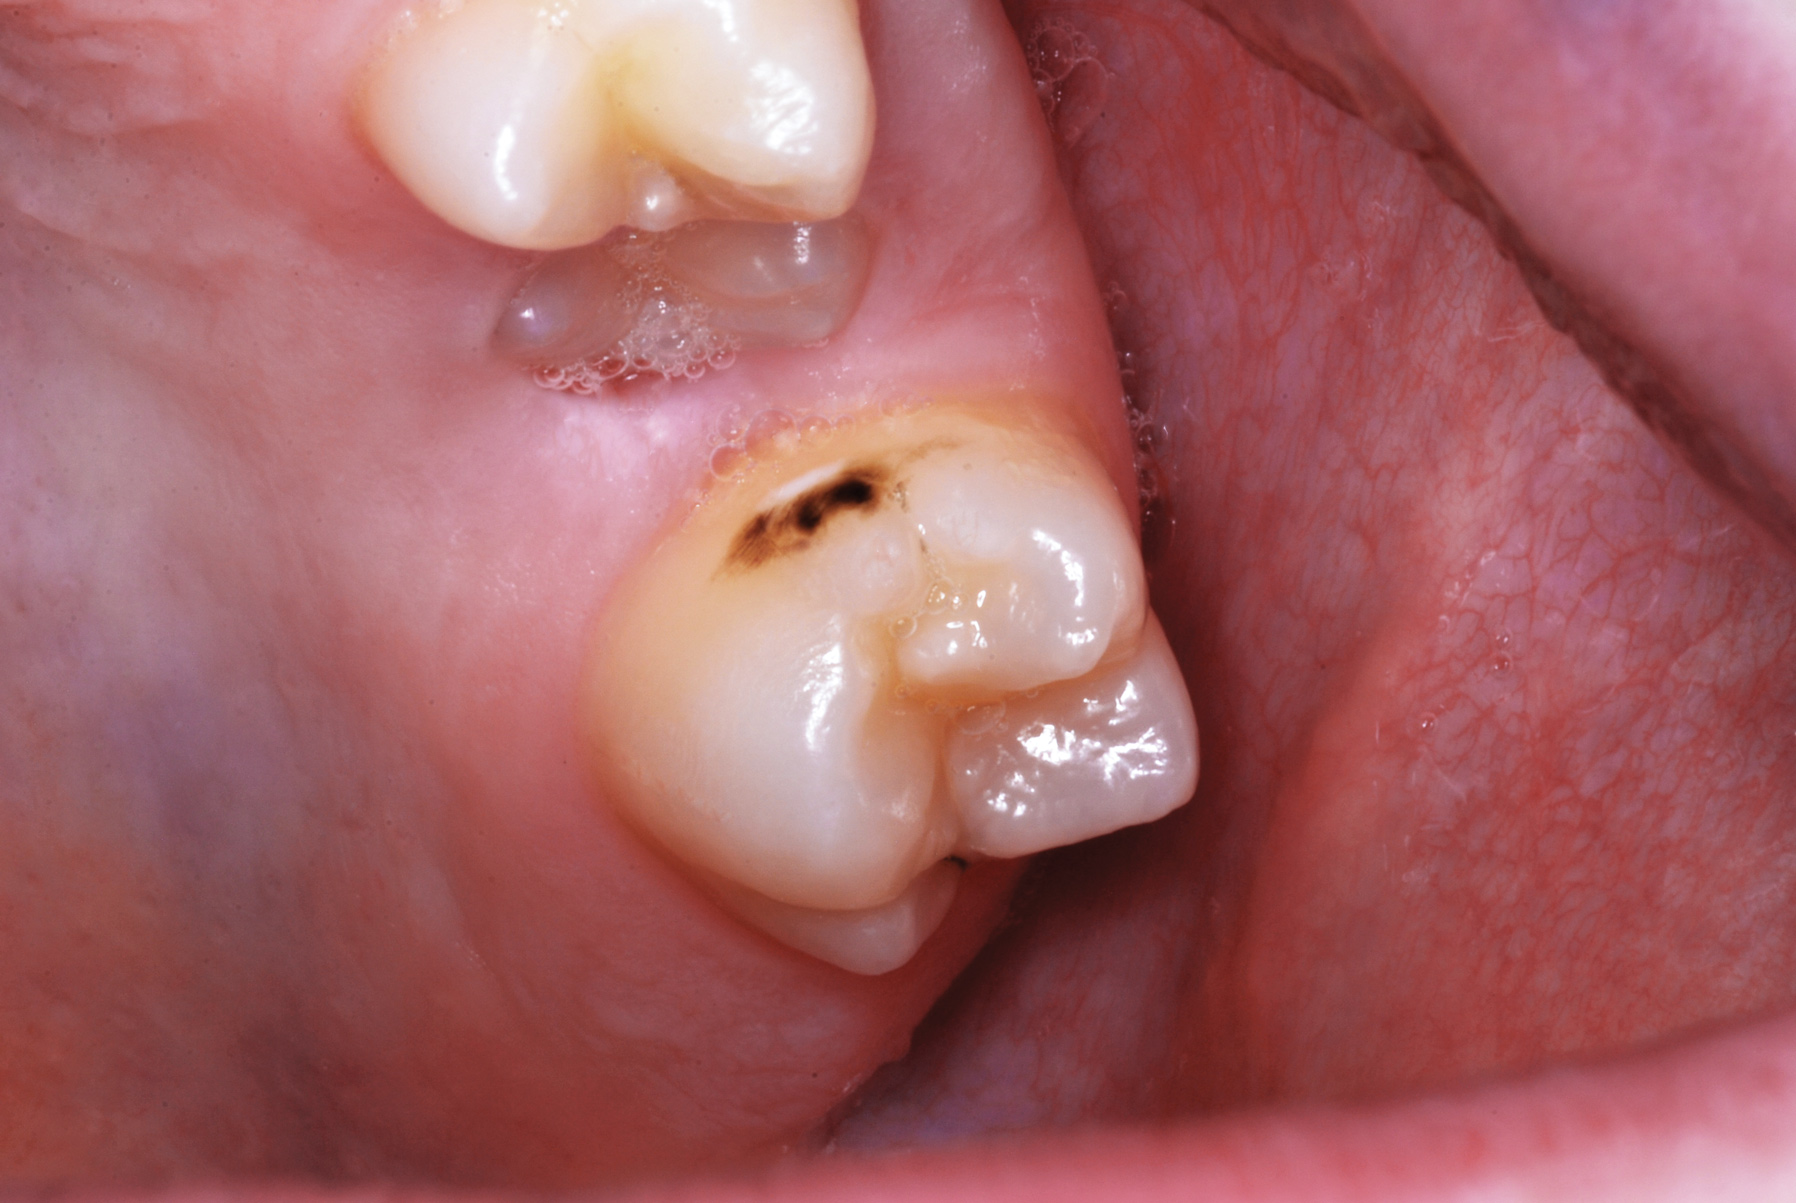

Arrested Caries

Arrested Caries What Is Arrested Dental Caries Arrested caries is a type of dental caries affecting teeth which are basically caries which has become stationary or. Dental caries and its complications can. Dental caries is a common chronic infectious disease that occurs in the dental hard tissues. Although the recommended interventions are often used for caries prevention, or in conjunction with restorative treatment options, these approaches have. What Is Arrested Dental Caries.